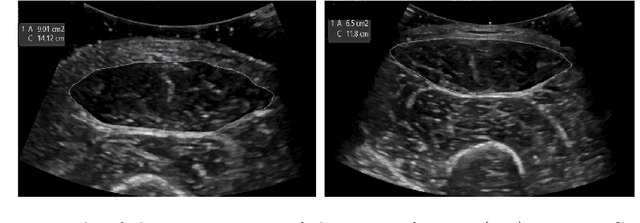

Abstract:Accurate analysis of prenatal ultrasound (US) is essential for early detection of developmental anomalies. However, operator dependency and technical limitations (e.g. intrinsic artefacts and effects, setting errors) can complicate image interpretation and the assessment of diagnostic uncertainty. We present L-FUSION (Laplacian Fetal US Segmentation with Integrated FoundatiON models), a framework that integrates uncertainty quantification through unsupervised, normative learning and large-scale foundation models for robust segmentation of fetal structures in normal and pathological scans. We propose to utilise the aleatoric logit distributions of Stochastic Segmentation Networks and Laplace approximations with fast Hessian estimations to estimate epistemic uncertainty only from the segmentation head. This enables us to achieve reliable abnormality quantification for instant diagnostic feedback. Combined with an integrated Dropout component, L-FUSION enables reliable differentiation of lesions from normal fetal anatomy with enhanced uncertainty maps and segmentation counterfactuals in US imaging. It improves epistemic and aleatoric uncertainty interpretation and removes the need for manual disease-labelling. Evaluations across multiple datasets show that L-FUSION achieves superior segmentation accuracy and consistent uncertainty quantification, supporting on-site decision-making and offering a scalable solution for advancing fetal ultrasound analysis in clinical settings.

Abstract:The current approach to fetal anomaly screening is based on biometric measurements derived from individually selected ultrasound images. In this paper, we introduce a paradigm shift that attains human-level performance in biometric measurement by aggregating automatically extracted biometrics from every frame across an entire scan, with no need for operator intervention. We use a convolutional neural network to classify each frame of an ultrasound video recording. We then measure fetal biometrics in every frame where appropriate anatomy is visible. We use a Bayesian method to estimate the true value of each biometric from a large number of measurements and probabilistically reject outliers. We performed a retrospective experiment on 1457 recordings (comprising 48 million frames) of 20-week ultrasound scans, estimated fetal biometrics in those scans and compared our estimates to the measurements sonographers took during the scan. Our method achieves human-level performance in estimating fetal biometrics and estimates well-calibrated credible intervals in which the true biometric value is expected to lie.